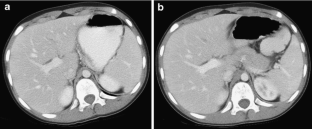

Fig. 2